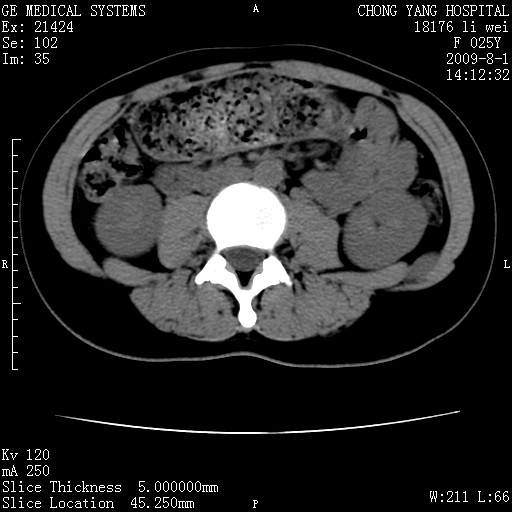

以下是引用pujunzhi在2009-8-1 20:23:00的发言:[br]胸椎旁及背部肌间良性病变,范围广,边界清,沿肌间生长,考虑淋巴管瘤、血管瘤,建议增强扫描。

以下是引用拾荒者在2009-12-30 21:45:00的发言:[br]ct21383:神经纤维瘤病( nf) [br] [br] 神经纤维瘤病。四肢都有,影响美观,四肢上的手术了。[br] [br] [br]谢谢!